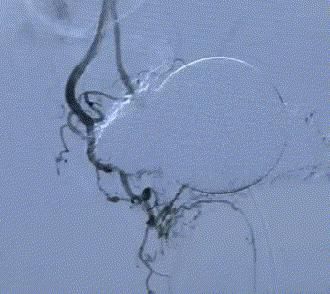

随後,李旭丹主任攜手胡志華主任爲患者實施介入治療,采用改良Seldinger法穿刺股動脈,在DSA引導下經動脈自然腔道,将微導管分别送達雙側髂内動脈進行造影,觀察雙側前列腺動脈分布情況,将微導管超選擇至雙側前列腺動脈,準确置入PVA栓塞材料,成功阻斷前列腺的營養供給,順利完成了治療。

△術後,前列腺供血動脈被成功阻斷。